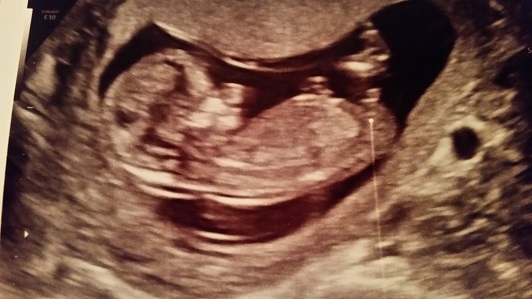

Pic from my 12 week 4 day ultrasound. Looks like a boy to me... what do you think?

I agree. Thinking boy.

Oh yeah, that is the EPITOME of a boy nub!

Thanks guys!! I will post the confirmation in a few weeks at our 17.5 week ultrasound!